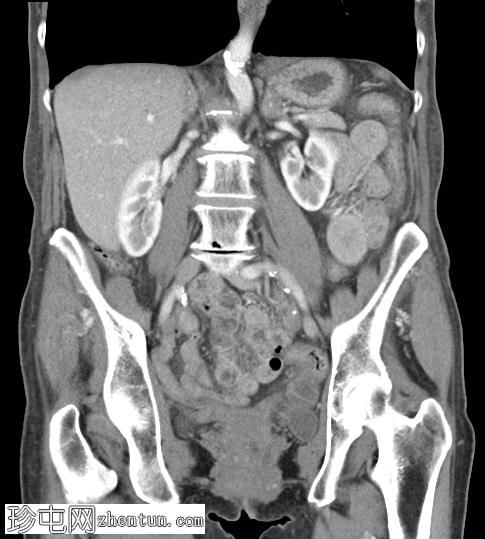

轴位增强扫描(门静脉期)

可见右侧股疝嵌顿,右侧股静脉受压,输出小肠袢塌陷,输入小肠袢扩张。可见中等量周围游离液体。无缺血征象。右侧努克氏管向内侧移位。疝颈位于腹壁下动脉起始部和腹股沟韧带下方。

肝脏可见多个小囊肿。左侧肾上腺肿大,内含低强化结节。

股总静脉受压、疝颈狭窄、女性、努克氏管向内侧移位、疝颈起源于腹壁下动脉起始部和腹股沟韧带下方等表现,更倾向于股疝而非腹股沟疝。